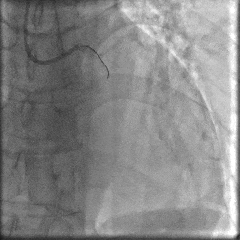

冠脉造影:

冠脉功能学全面评估:

▶IMR:80(+);CFR:1.0(+);FFR:0.82。